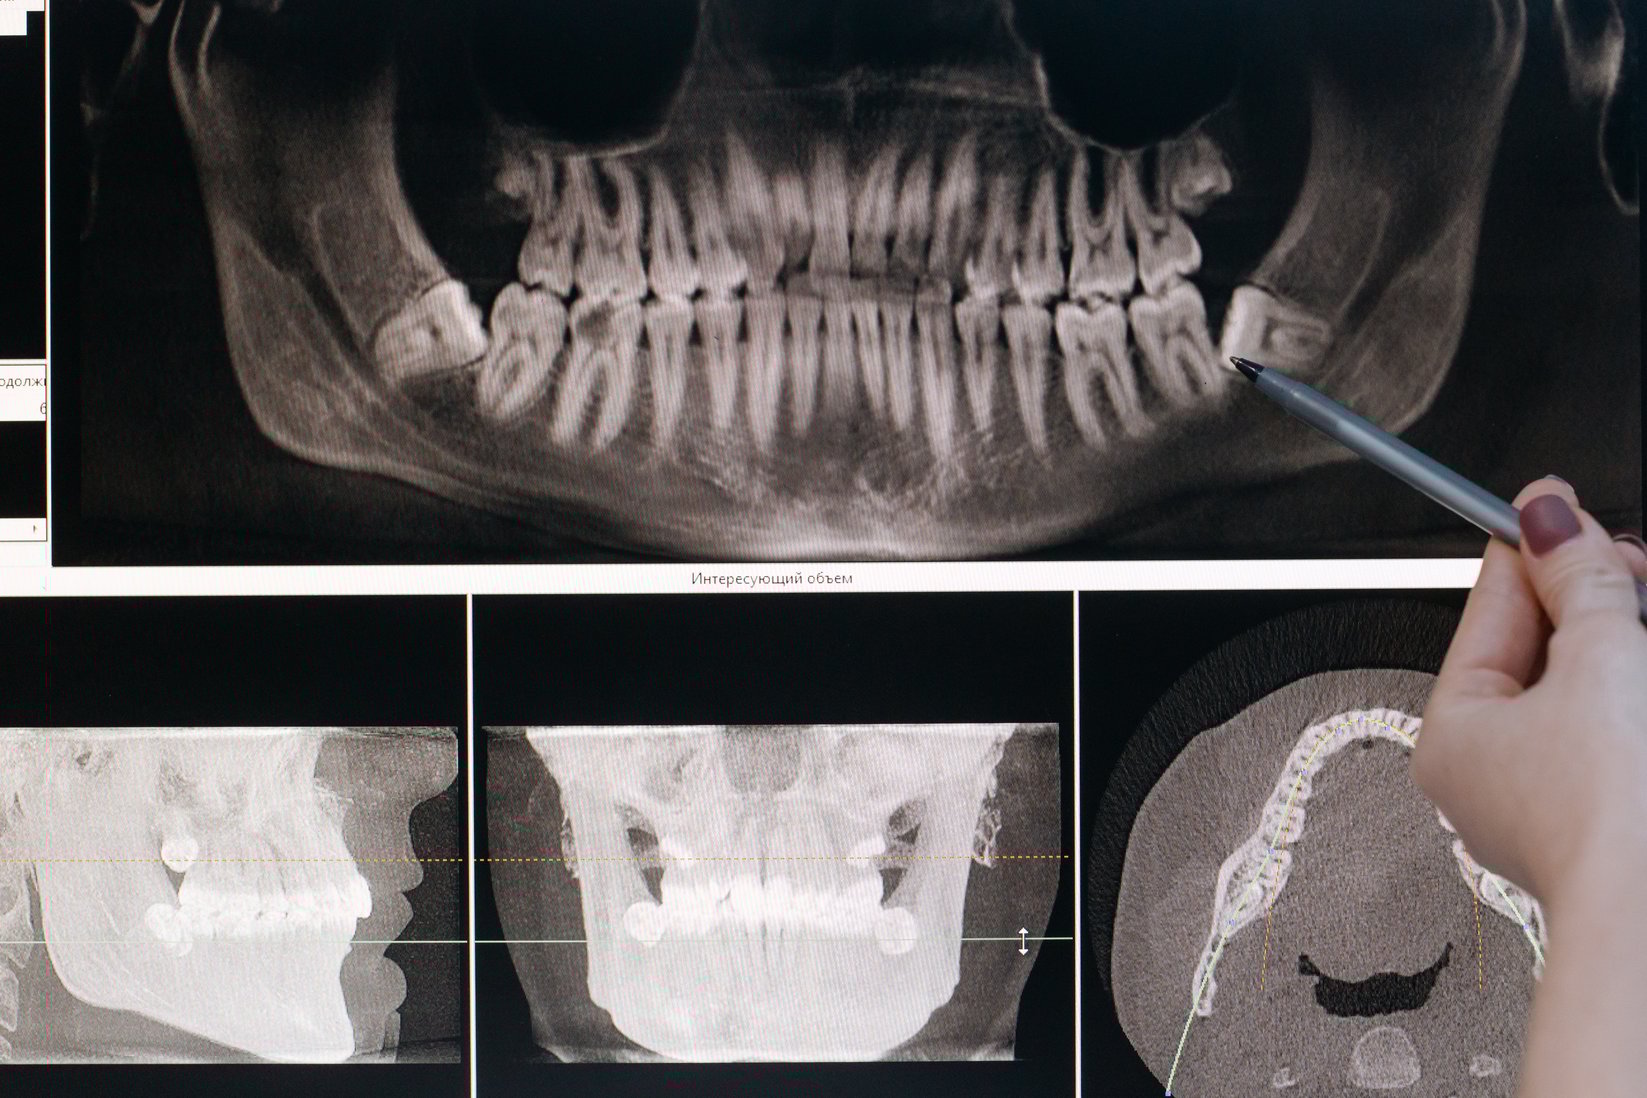

What Holds Your Teeth In Their Socket . The periodontal ligament is the fibrous connective tissue found between the roots of the teeth and the inner wall of the alveolar bone socket. This support is crucial for. The alveolar bone is the bone of the jaw that contains the tooth sockets (also known as dental alveoli or alveolar process) on bones that hold teeth. The periodontal ligament (pdl) is the soft tissue union between your teeth and the bone. The teeth are connected with the walls of the tooth sockets and anchored in the jaws by the periodontal ligament and the cementum. The pdl fibers support your teeth in their sockets and help to keep the gingival tissues (gums) in the proper relationship with your teeth and the alveolar bone. It is widely, and mistakenly, believed that gum tissue and bone hold the teeth in place. Many people think teeth are held in by the bone. In reality, the periodontal ligament (pdl) serves as a soft. It is located in the socket of each tooth, and it serves as the anchor that holds the teeth in place within their sockets. The tooth root is an integral part of the basic anatomy of a tooth.